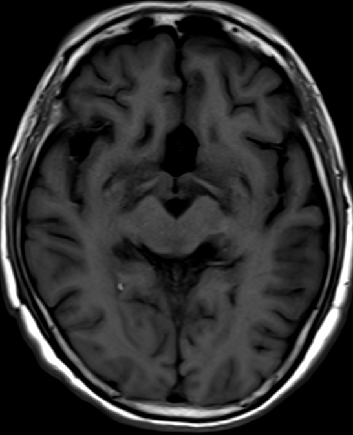

2013-5-16 MRI